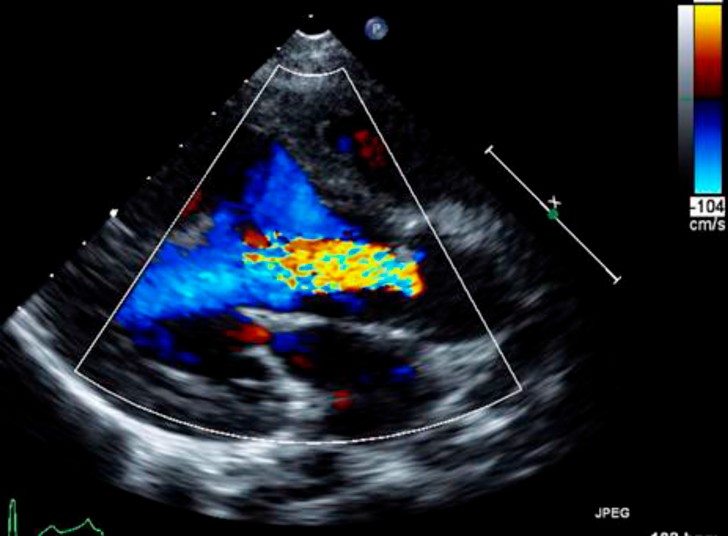

大動脈縮窄術後再狭窄および大動脈弁閉鎖不全症に対して側開胸を併施した正中アプローチによる再手術の1例Combined Full Median Sternotomy with Left Thoracotomy Approach for Recoarctation of the Aorta Associated with Aortic Regurgitation